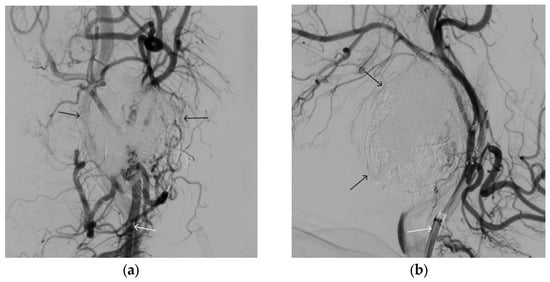

A 48-year-old male patient was admitted to the clinic with complaints of a subcutaneous volume formation in the lower jaw area on the left. Earlier, in another clinic, an attempt was made to embolize the AVM using microcoils. Angiography was performed; filling of the AVM of the soft tissues of the face in the area of the angle of the lower jaw on the left was noted. The presence of separable coils in the afferent from the previous operation was noted; however, the AVM was filled through the coils (Figure 8 and Figure 9). Total embolization of the AVM of the face soft tissues with 7.5 mL of non-adhesive composition ONYX18 was performed. Arteriovenous malformation was totally shut down (Figure 10). There were no complications. The mRs score at discharge was 0.

Figure 6. Digital subtraction angiography from the right and left facial arteries: (a) direct projection; (b) lateral projection (white arrows indicate catheters at the ostium of the facial arteries, black arrows indicate embolizate cast). The absence of AVM contrast is noted.